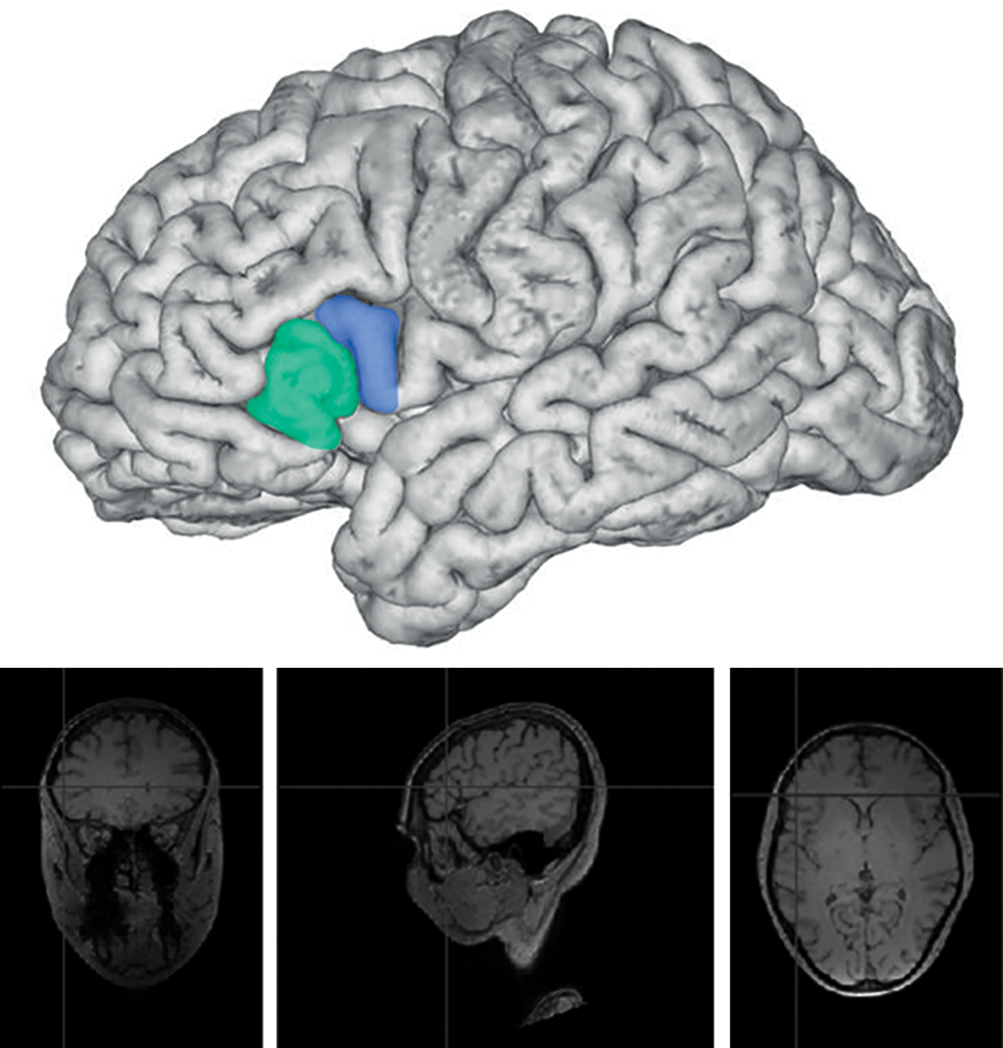

Установлены принципиальные изменения строения мозга мужчин-музыкантов в сравнении с мозгом мужчин контрольной группы и мозга женщин-музыкантов в сравнении с мозгом женщин контрольной группы. При сравнительном анализе макроскопического строения зоны Брока левого полушария (ЛП) мозга у женщин-музыкантов установлено более сложное строение триангулярной области коры мозга мозга, чем у женщин контрольной группы. В мозге женщин-музыкантов в сравнении с мозгом женщин контрольной группы отмечается наличие дополнительных бороздок, особенно в триангулярной области, и слияние триангулярной области с оперкулярной областью и орбитальной областью мозга за счёт наличия межуточных формаций, увеличивающих размеры как триангулярной, так и оперкулярной области (рис. 1, 2).

Рис. 1. Строение зоны Брока мозга женщины-музыканта, ЛП. Зелёным цветом обозначена триангулярная область, синим — оперкулярная.

Fig. 1. Structure of Broca’s area in the brain of a female musician, LH. Triangular region is shown in green; opercular region is shown in blue.